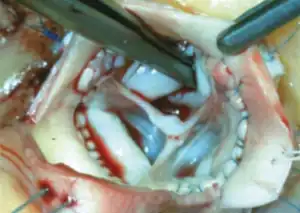

Before the operation, preparations include transthoracic echocardiography and measurements of the ascending aorta and the pulmonary valve.[10] Under general anaesthesia, the chest is cut open in the midline.[5] The heart and aorta are exposed before the heart is temporarily stopped and its function taken over cardiopulmonary bypass.[5] Subsequent steps include removing the diseased aortic valve and mobilizing the coronary arteries, followed by harvesting and preparing the person's own healthy pulmonary valve, before implanting it within the left ventricular outflow tract, the exit of the left side of the heart (where the aorta begins).[2][10] Then the coronary artery is reimplanted, before the pulmonary homograft is implanted in the right ventricular outflow tract, the exit of the heart's right side (where the pulmonary artery begins).[2][10] The pulmonary autograft is joined with the ascending aorta.[2][10]

Ross technique

Ross technique: subcoronary method